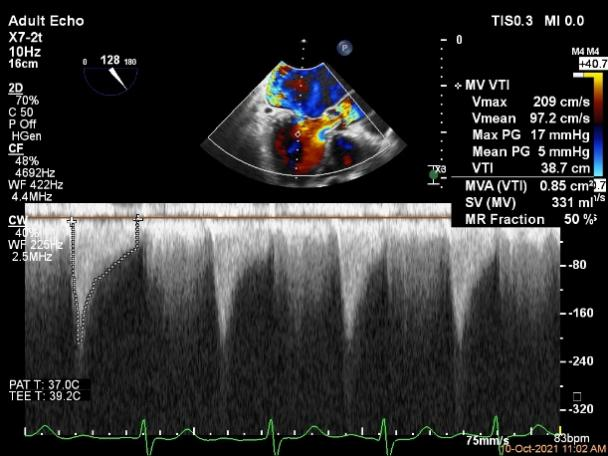

3D-color MV view:极大量返流,1、2区均有受累

Qlab软件勾画估测瓣口面积约:6.23cm²

第一个夹子放置后二尖瓣口平均跨瓣压差:4mmHg

第二个夹子放置后二尖瓣口平均跨瓣压差:4mmHg